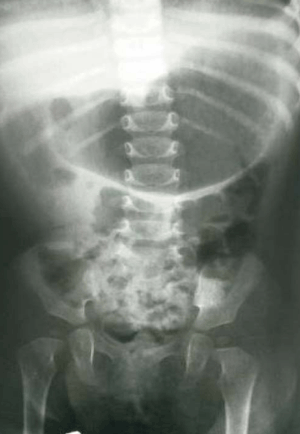

Se reiteran estudios imagenológicos con una nueva ecografía abdominal que muestra dilatación de cámara gástrica marcada y de las dos primeras porciones del duodeno e imagen sugestiva de obstrucción duodenal parcial a nivel de D2. La (Figura 3) muestra la radiografía de abdomen de pie gran dilatación gástrica, con signo de la doble burbuja. La (Figura 4) y la (Figura 5) muestran el estudio contrastado gastroduodenal que constató obstrucción duodenal a nivel de segunda porción con pasaje a sectores distales. Sin evidencias de malrotación u otras anomalías.

Figura 4: Estudio radiológico contrastado gastroduodenal. Se observa obstrucción en D2 con pasaje de contraste distal.

Figura 5: Estudio radiológico contrastado gastroduodenal. Se observa obstrucción en D2 con pasaje de contraste distal.

En este caso el estudio contrastado confirmó la obstrucción duodenal parcial, se destaca la importancia del mismo como examen para el diagnóstico de obstrucción duodenal, su topografía, y descartar diagnósticos diferenciales como malrotación intestinal, especialmente en los casos que se presentan con síntomas crónicos de obstrucción parcial duodenal1. Si bien la radiografía simple de abdomen orientaba a la topografía duodenal, el estudio contrastado digestivo alto es fundamental, ya que confirma la topografía en el 70% de los casos11.